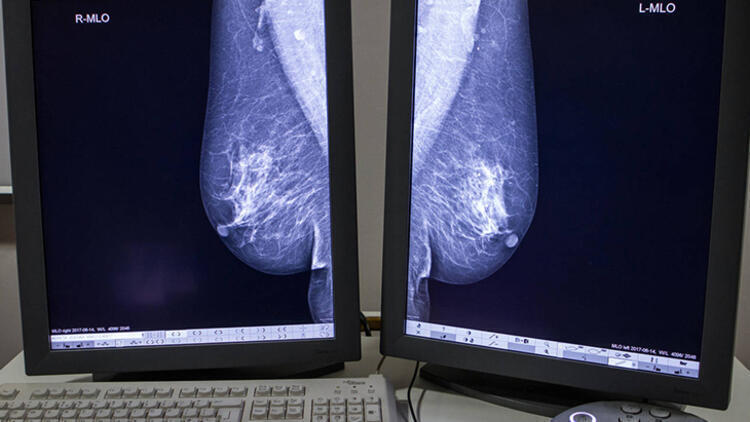

Meme kanseri ile ilgili bilinmesi gereken 15 gerçek